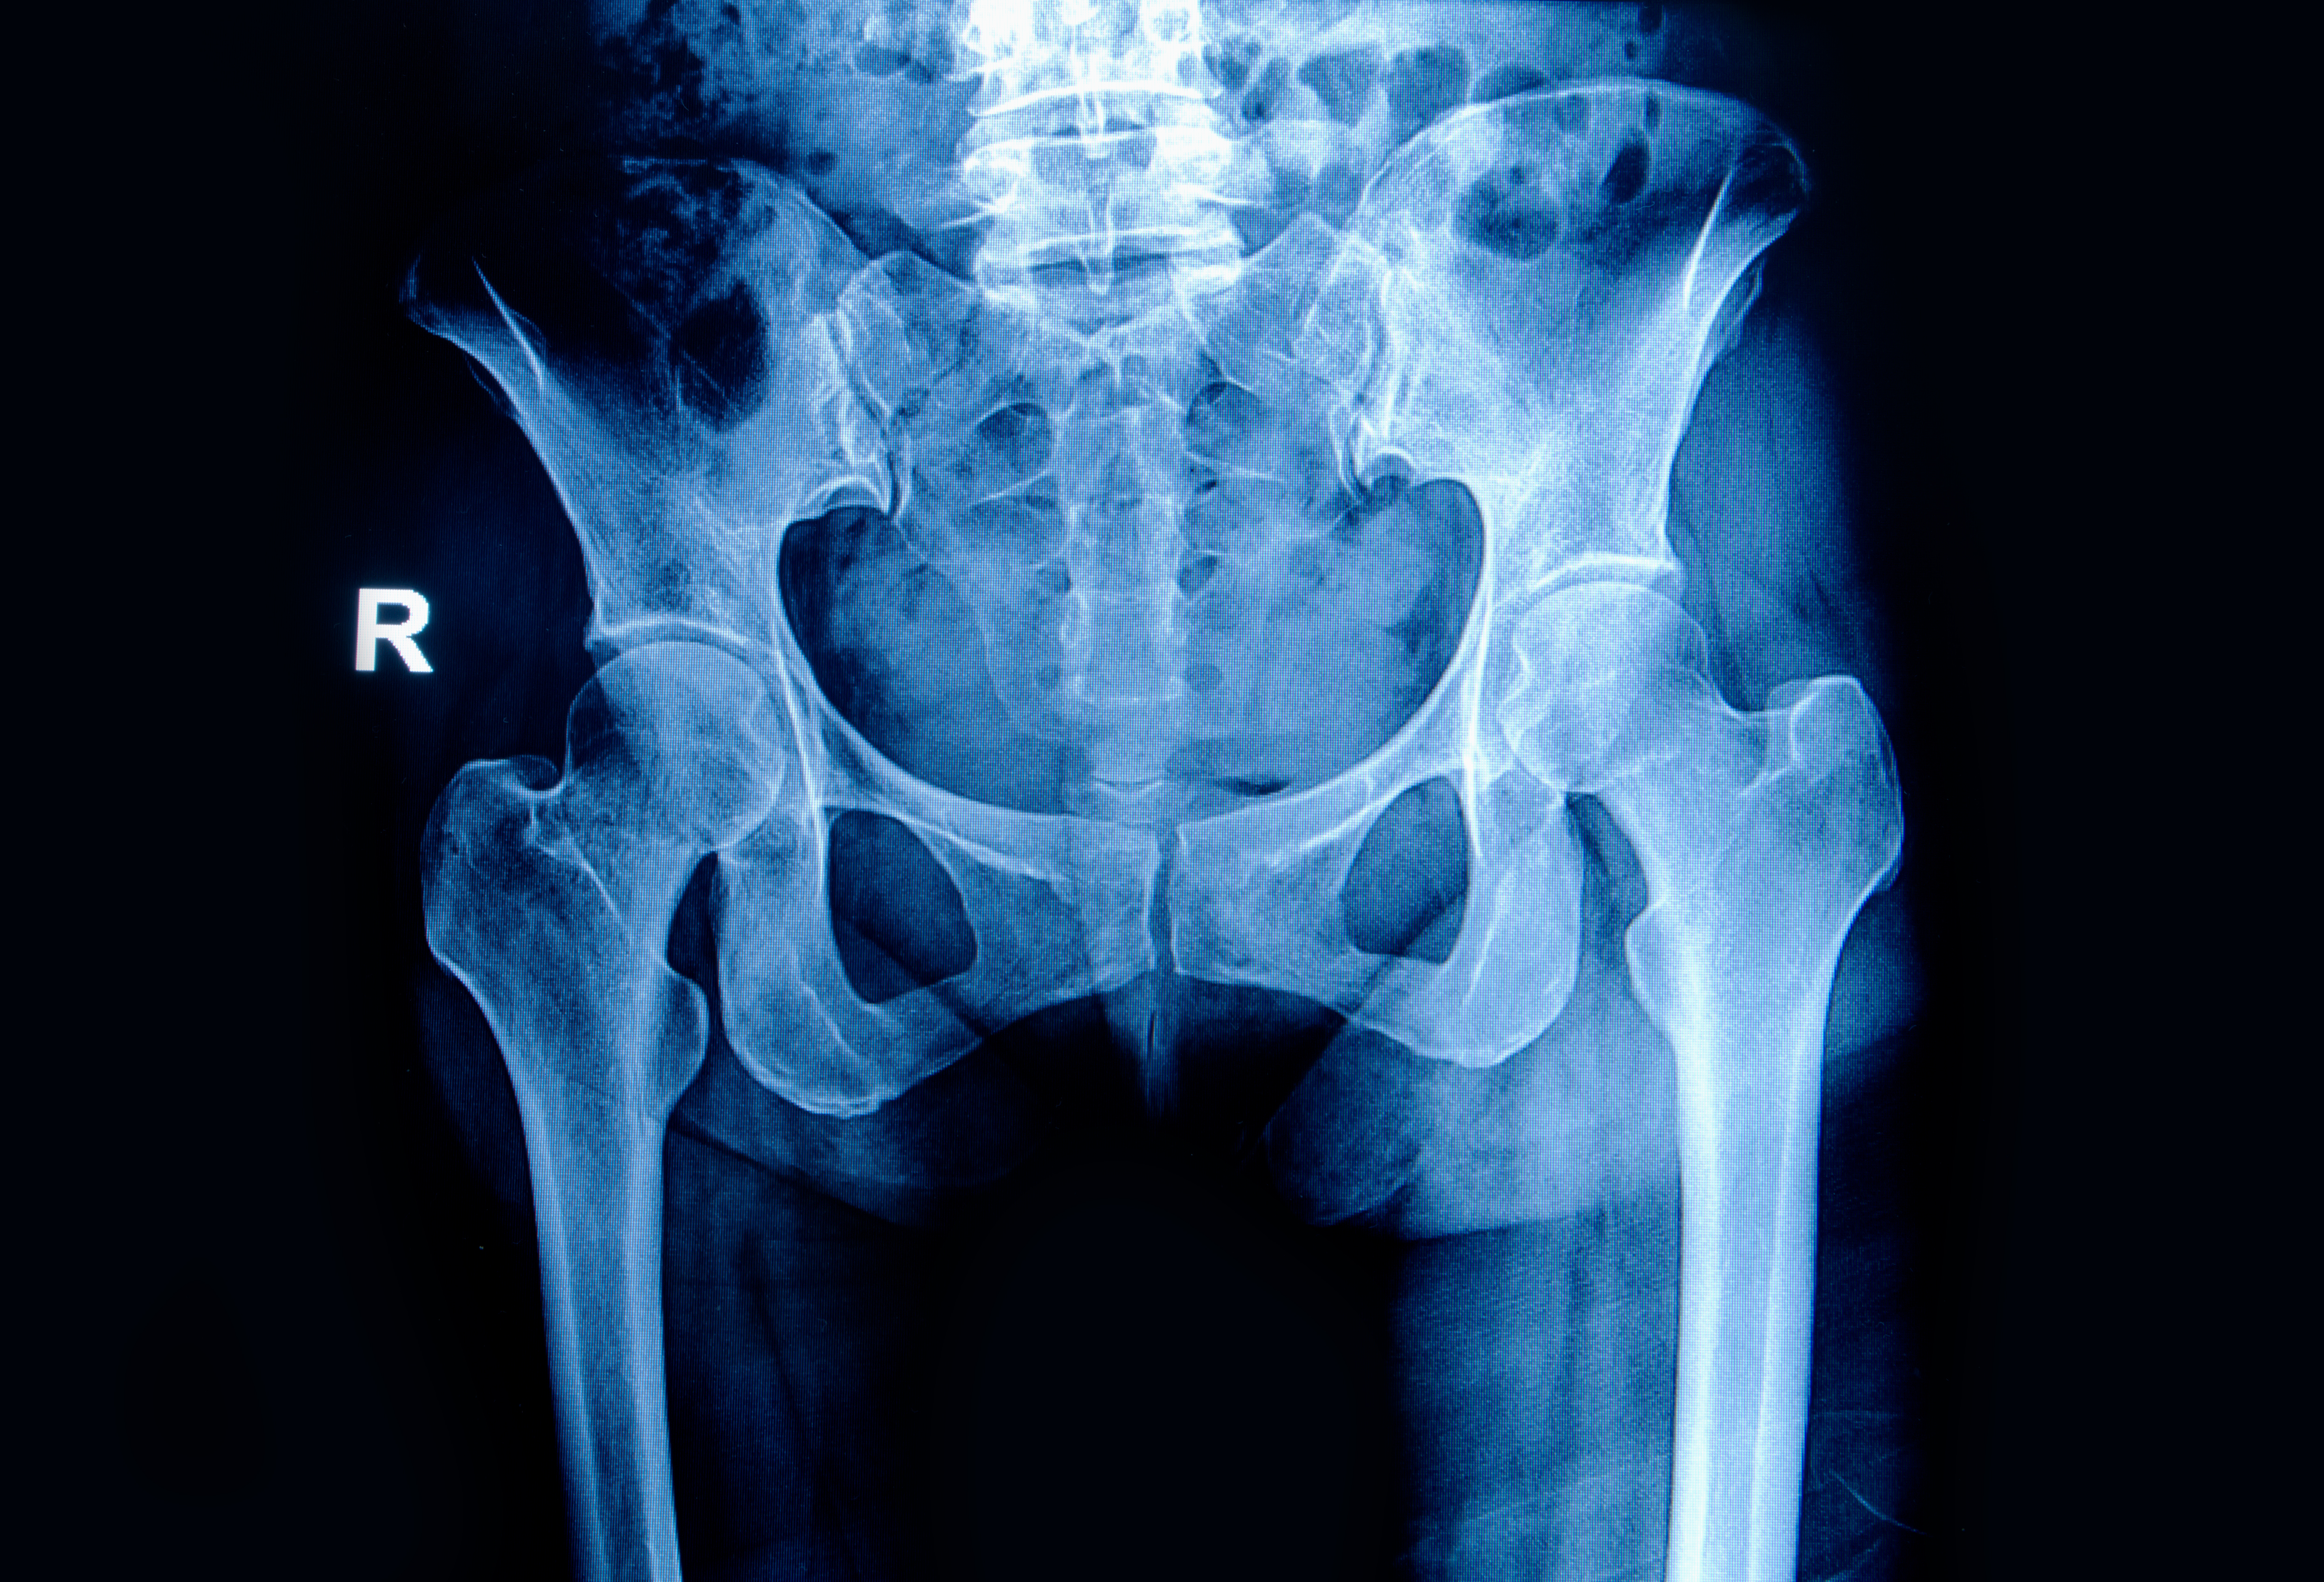

Foto: Colourbox

Å pådra seg hoftebrudd når man er passert 65 år er uten tvil en stor påkjenning for kroppen. Fra tidligere er det kjent at denne pasientgruppen har høy dødelighet etter hoftebruddet. En fersk studie av 37 708 hoftebrudd i Norge i perioden 2014–2018 viser at disse pasientene har en betydelig kortere forventet levetid sammenliknet med en sammenliknbar del av befolkningen.